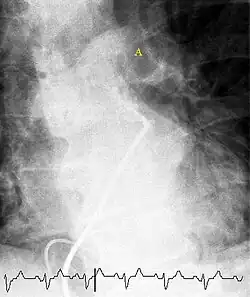

CT pulmonary angiography

CT pulmonary angiography (CTPA) is a pulmonary angiogram obtained using computed tomography (CT) with radiocontrast rather than right heart catheterization. Its advantages are that it is accurate, it is non-invasive, it is more often available, and it may identify other lung disorders in case there is no pulmonary embolism. The accuracy and non-invasive nature of CTPA also make it advantageous for people who are pregnant.[61]

-

On CT scan, pulmonary emboli can be classified according to the level along the arterial tree. -

Segmental and subsegmental pulmonary emboli on both sides -

CT pulmonary angiography showing a "saddle embolus" at the bifurcation of the main pulmonary artery and thrombus burden in the lobar arteries on both sides

Assessing the accuracy of CT pulmonary angiography is hindered by the rapid changes in the number of rows of detectors available in multidetector CT (MDCT) machines.[62] According to a cohort study, single-slice spiral CT may help diagnose detection among people with suspected pulmonary embolism.[63] In this study, the sensitivity was 69% and specificity was 84%. In this study which had a prevalence of detection was 32%, the positive predictive value of 67.0% and negative predictive value of 85.2%. However, this study's results may be biased due to possible incorporation bias, since the CT scan was the final diagnostic tool in people with pulmonary embolism. The authors noted that a negative single-slice CT scan is insufficient to rule out pulmonary embolism on its own. A separate study with a mixture of 4-slice and 16-slice scanners reported a sensitivity of 83% and a specificity of 96%, which means that it is a good test for ruling out a pulmonary embolism if it is not seen on imaging and that it is very good at confirming a pulmonary embolism is present if it is seen. This study noted that additional testing is necessary when the clinical probability is inconsistent with the imaging results.[64] CTPA is non-inferior to VQ scanning, and identifies more emboli (without necessarily improving the outcome) compared to VQ scanning.[65]